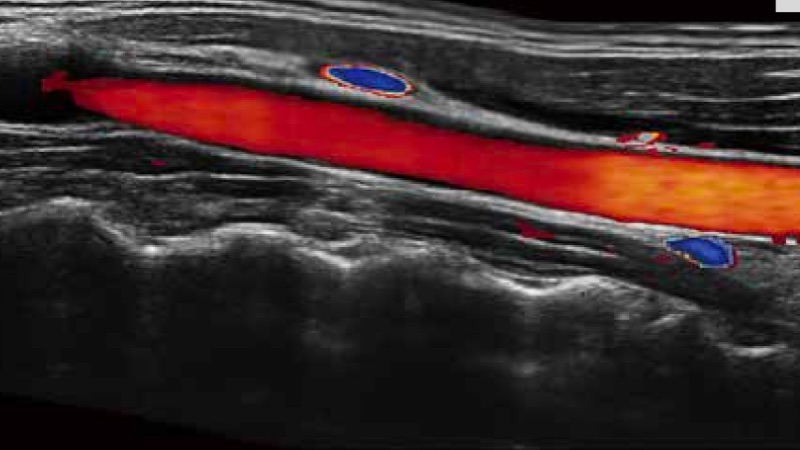

凭借狗万官方网站先进的成像技术和优异的探头技术提供的清晰的图像表现,您可以更自信地做出临床决策。